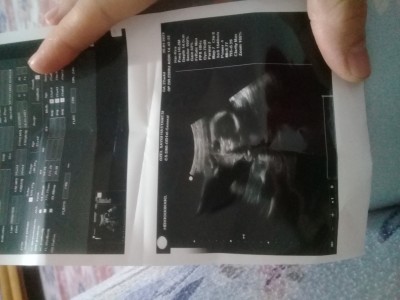

sizden cinsyet tahmini istyorm

Kıza benzettim ben toplanmış gibi, 22 haftalık olmuş neden ogrenmediniz daha cinsiyetini ben 17 haftalıkken öğrendim

Erkek gibi

Bence erkek

Kız geçti içimden

Kizz bencee...

İmmm pipi göremedim kız kız ☺️☺️